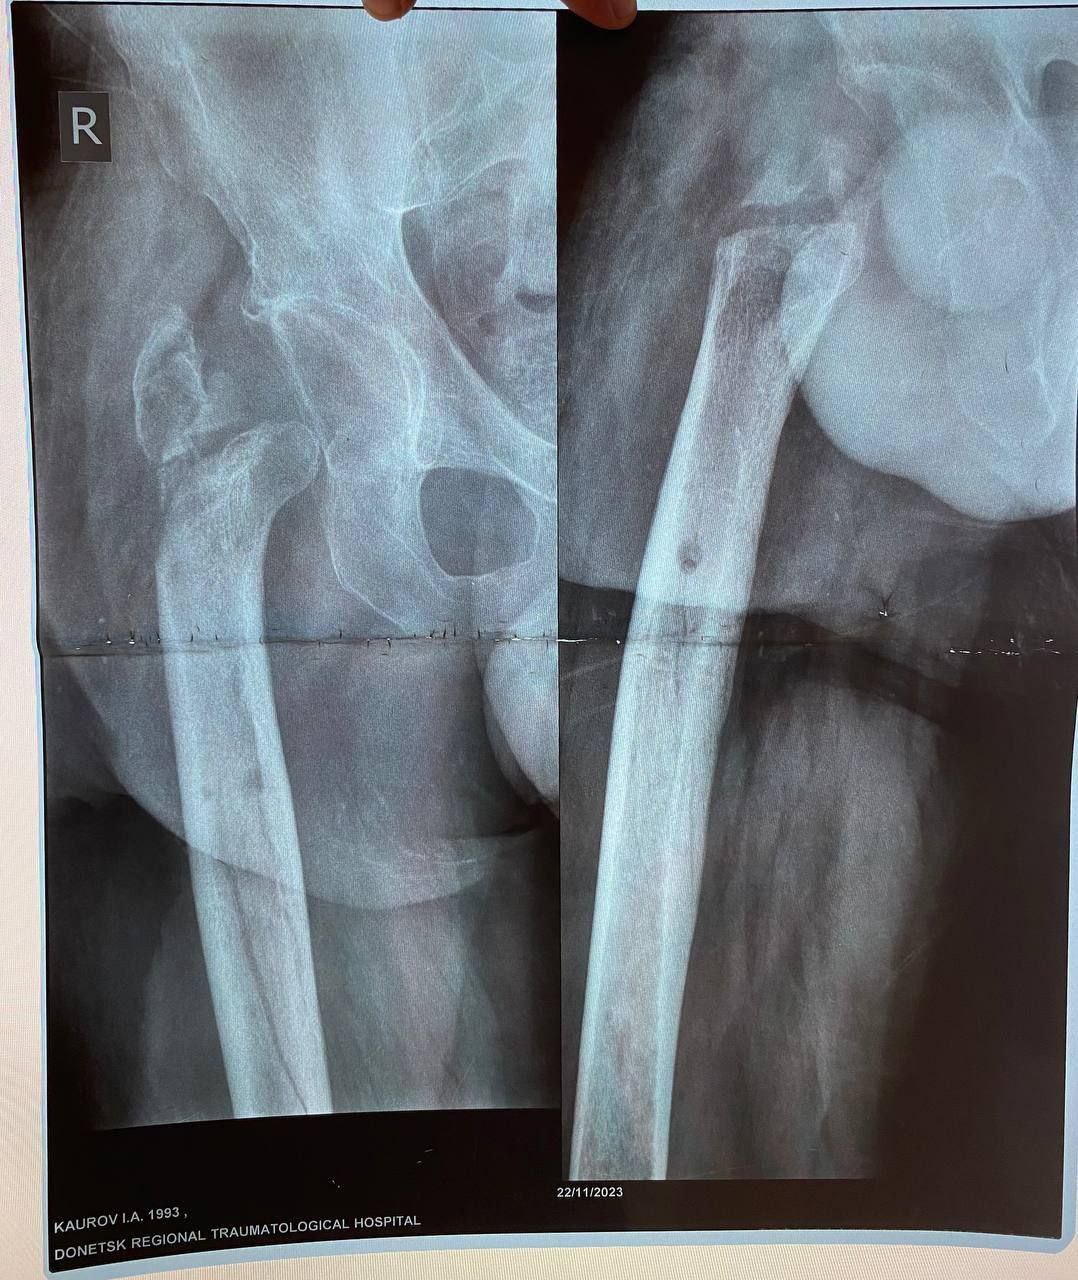

Пациентом стал 32-летний Илья из ЛНР, мобилизованный 25 февраля 2022 года.Сержант получил тяжелейшее осколочное ранение правого бедра под Херсоном 28 августа 2022 года.За три с половиной года боец прошёл через десять госпиталей, включая ЦВКГ им. Вишневского в Москве и ВМА им. Кирова в Санкт-Петербурге, перенёс множественные операции по удалению некрозов и остеосинтезу.

К моменту увольнения со службы в июле 2024 года основная проблема оставалась нерешённой: правая нога была короче левой почти на 9 сантиметров. Стандартное протезирование в такой ситуации неэффективно.

Хирургам ЛРКБ предстояло работать в рубцово-изменённых тканях после десятка предыдущих вмешательств, устранить очаги инфекции и с помощью специальных ревизионных компонентов восстановить биологическую ось конечности и вернуть ей физиологическую длину.